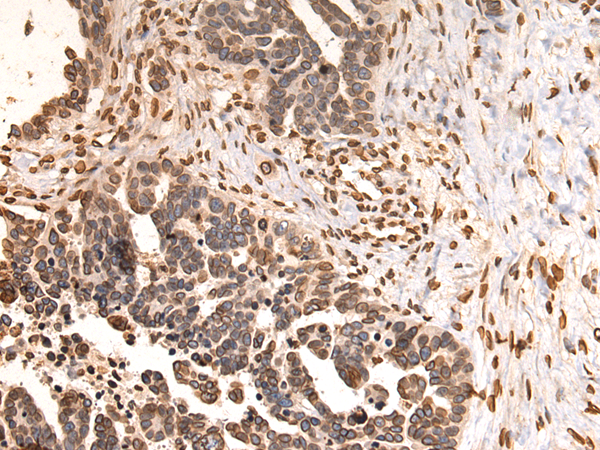

分类: 科研抗体货号: P07431别名: CMT2; RP1-261G23.6应用: WB,IHC反应种属: Human

分类: 科研抗体货号: P07422别名: FPL; IDC; LFP; CDDC; EMD2; FPLD; HGPS; LDP1; LMN1; LMNC; MADA; PRO1; CDCD1; CMD1A; FPLD2; LMNL1; CMT2B1; LGMD1B应用: WB,IHC反应种属: Human, Mouse, Rat